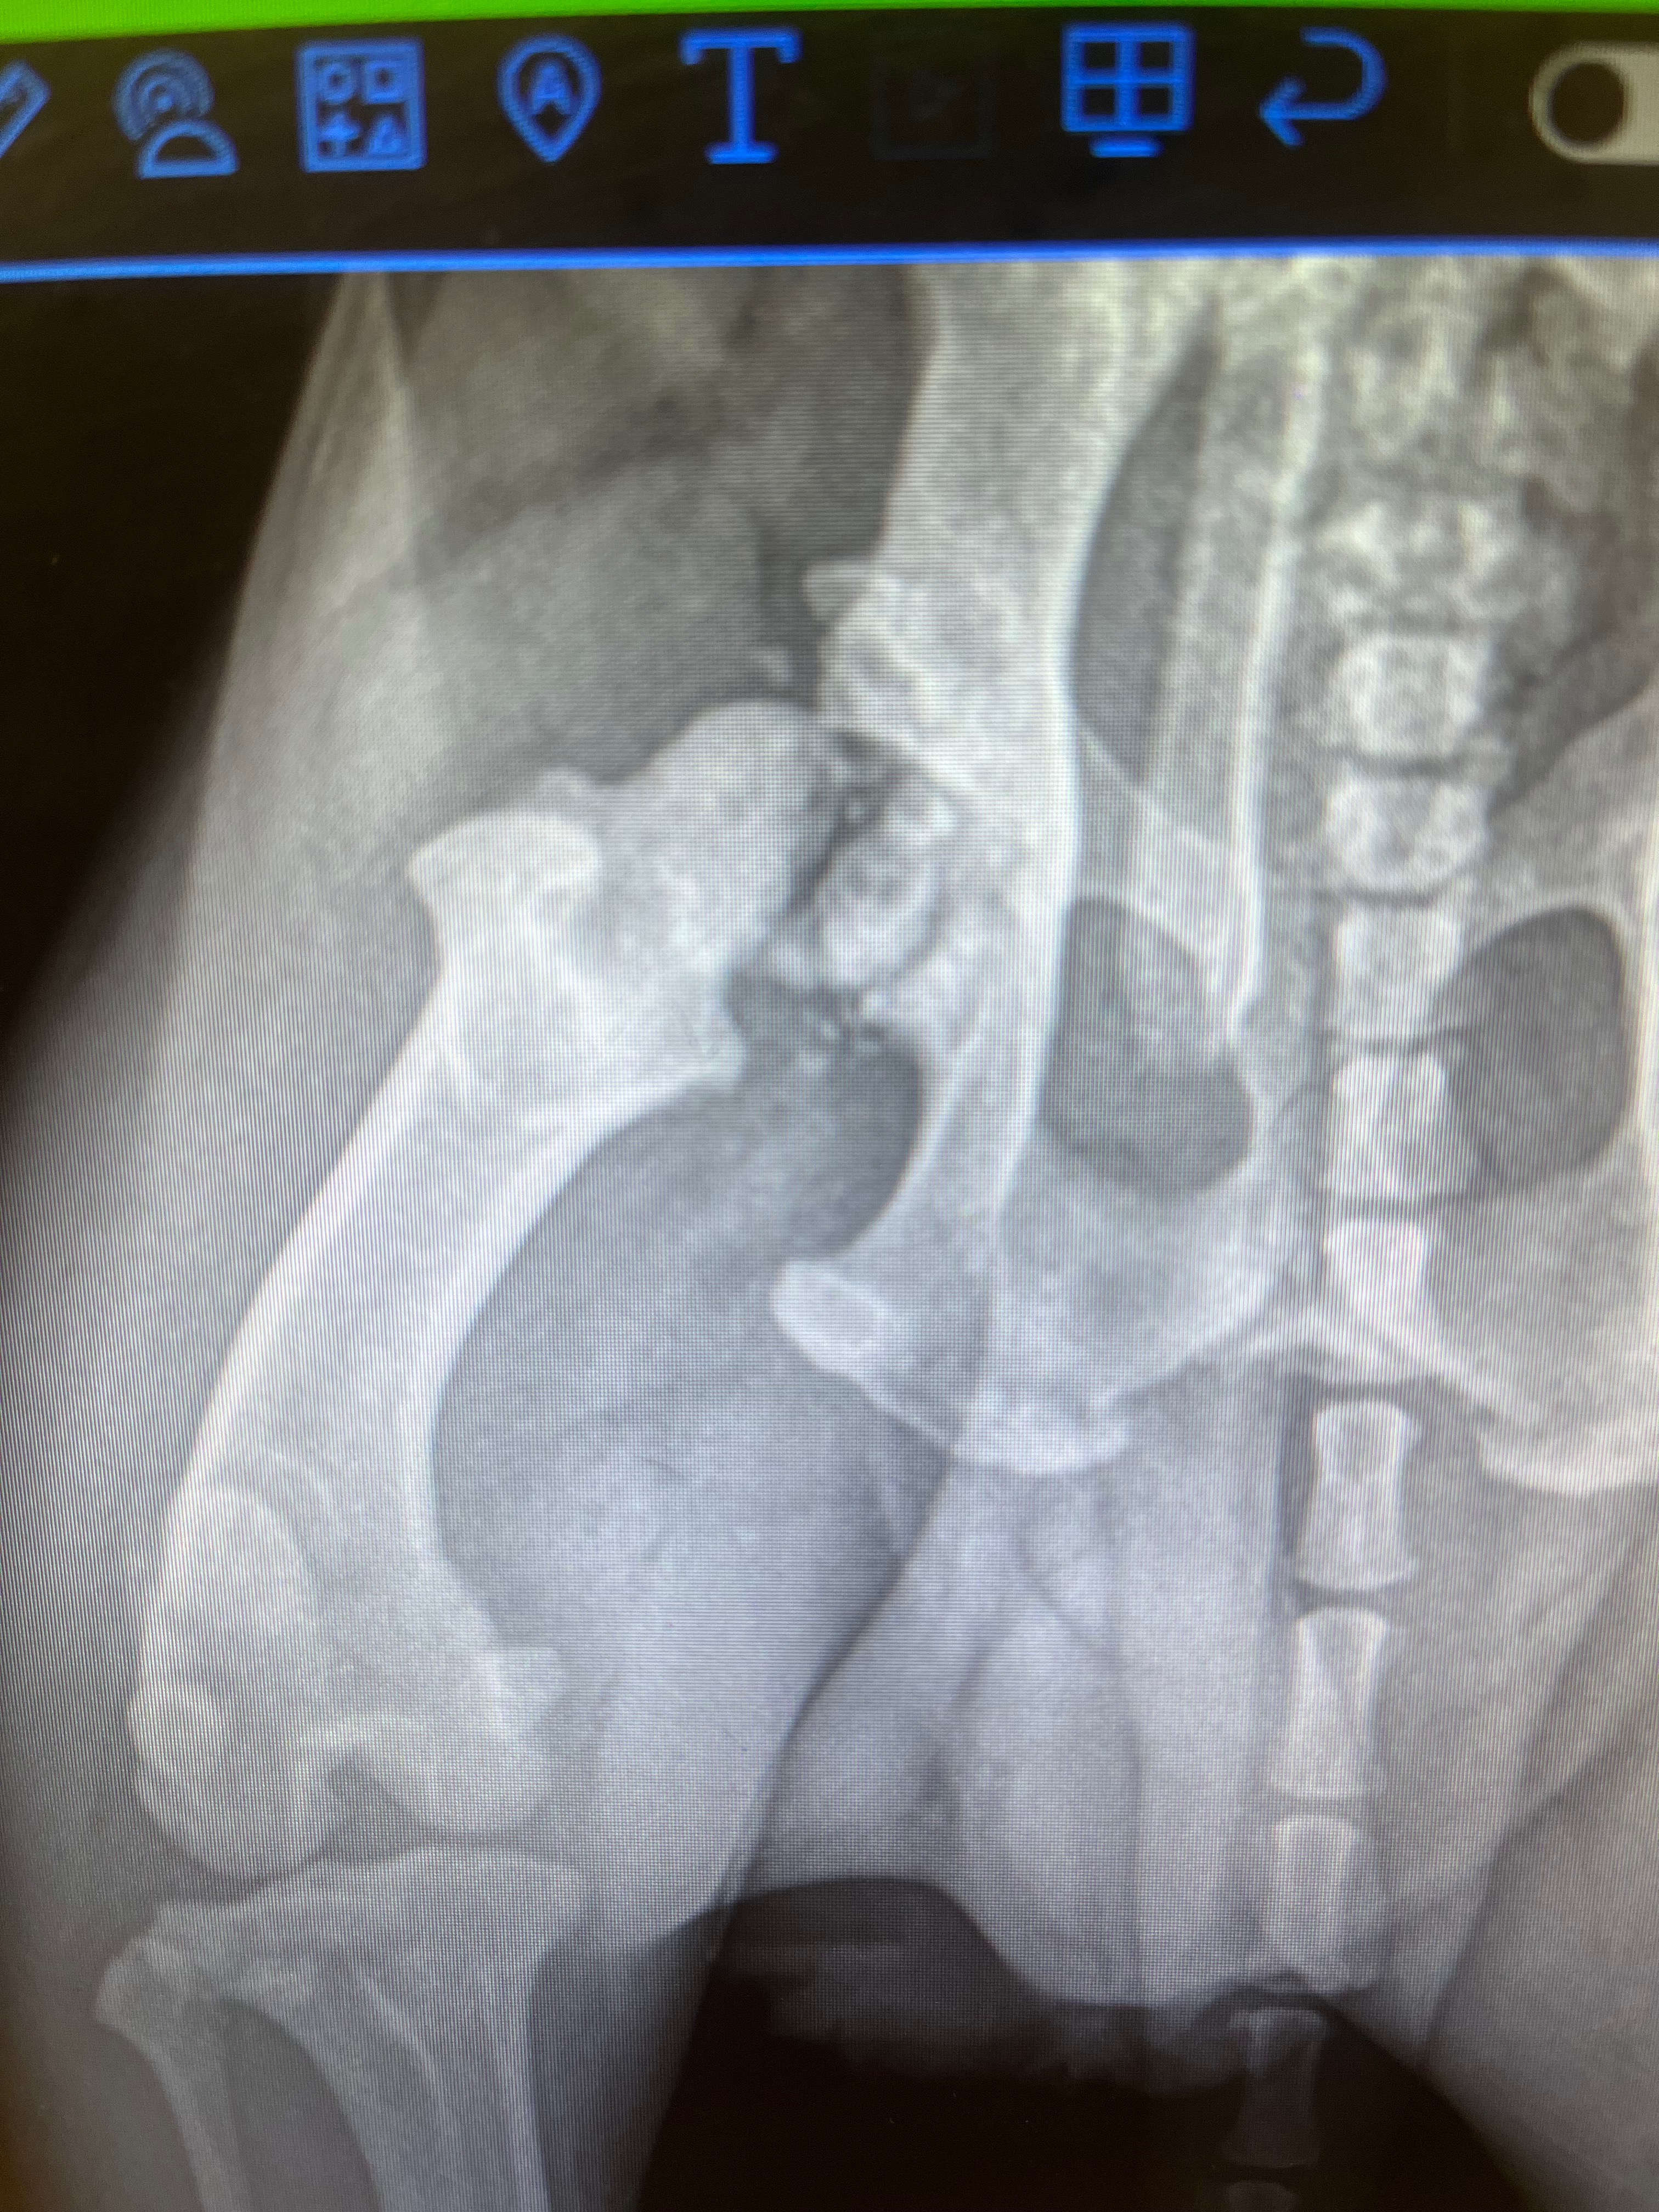

This cute little guy was found by a good samaratin, dumped in a field left with a bowl and a bag of dog food! Instantly trusting of humans he hopped in their car to safety. Now Blackjack is in our care awaiting his forever home but he’s got a hurdle to cross: Upon intake we noticed he had a limp, and thru X-rays it was discovered that he had suffered an old injury breaking the top of his femur bone! An FHO surgery will go in and clean up the small bits of broken bone that is causing his discomfort and he’ll be ready to live out an active, happy life. Help us get this boy on the road to his bright new future!